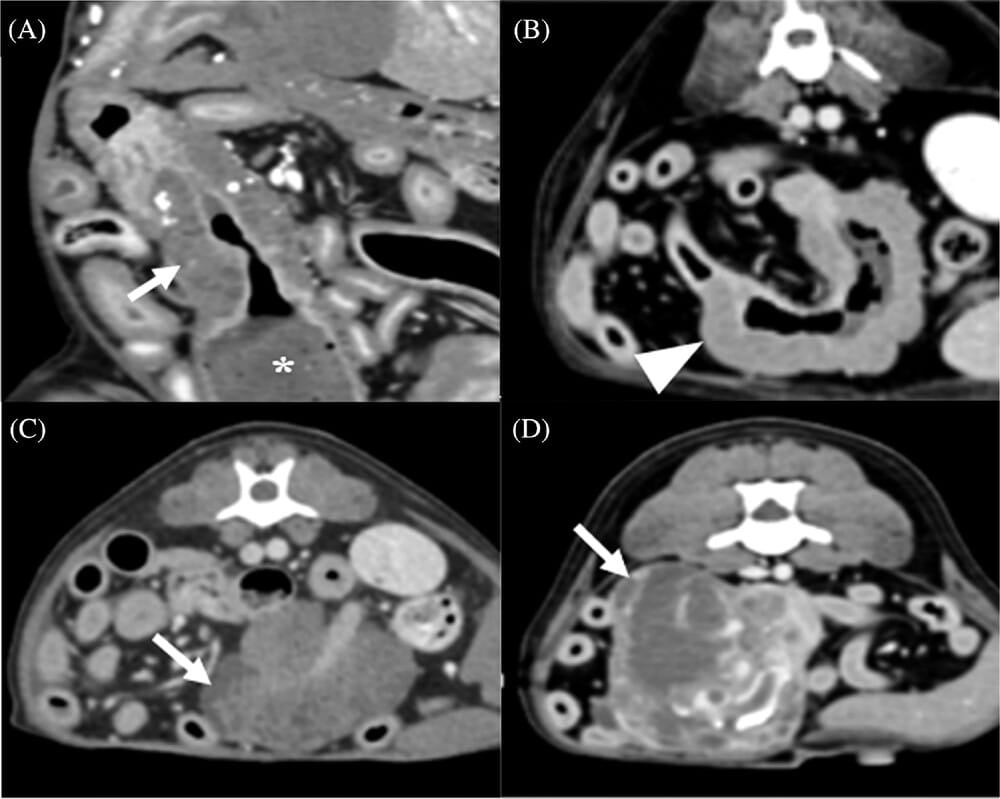

Postcontrast dorsal planar (A) and transverse (B–D) CT images representing the type of tumor growth in small intestinal tumors. A, Endophytic growth with tumoral changes toward the lumen of the small intestine (arrow) and with small intestinal dilation (asterisks). B, Exophytic growth with tumoral changes toward the outer wall of the small intestine (arrow). C,D, Lobulated growth without intestinal morphology (arrows)